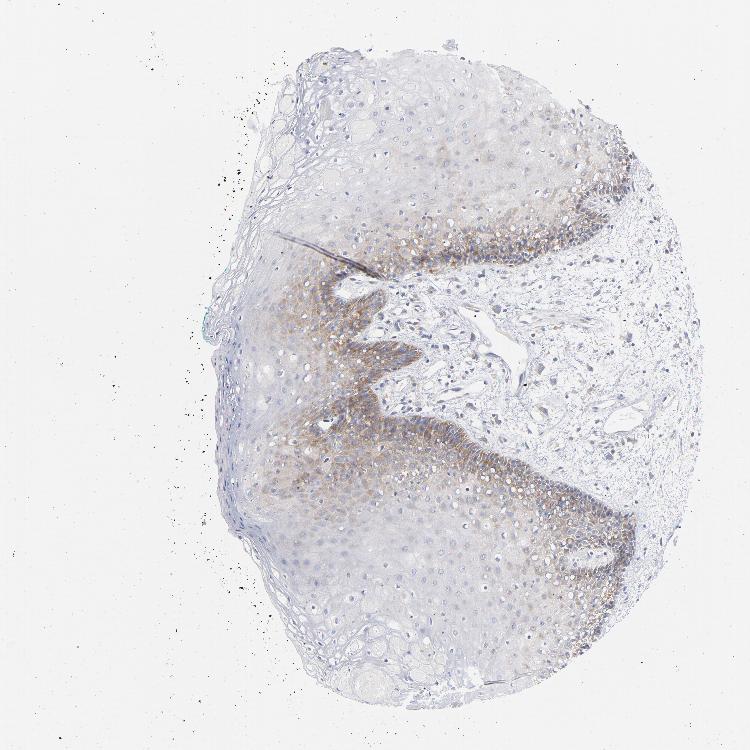

TISSUE PRIMARY DATA ORAL MUCOSA Show tissue menu

ORAL MUCOSA - Antibody stainingi

Antibody staining in the annotated cell types in the current human tissue is reported as not detected, low, medium, or high, based on conventional immunohistochemistry profiling in selected tissues. This score is based on the combination of the staining intensity and fraction of stained cells.

Each image is clickable and will lead to virtual microscopy that enables deeper exploration of all samples and also displays staining intensity scores, fraction scores and subcellular localization as well as patient and tissue information for each sample.

Antibody CAB004319

Squamous epithelial cells Low